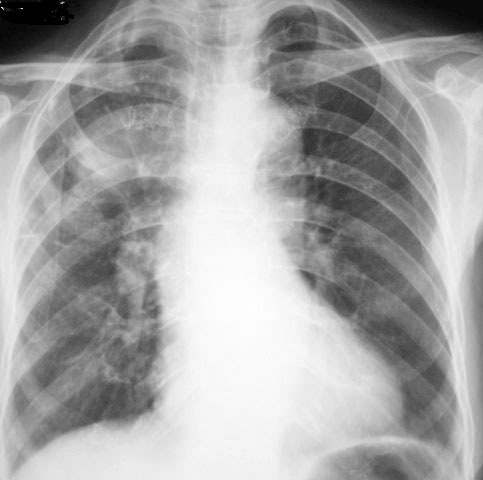

以下是引用随光逐影在2010-4-4 17:47:00的发言:[br]右上肺肿块,不排除肿瘤性病变;建议行ct扫描检查。

以下是引用zxl51642在2010-4-4 15:11:00的发言:[br]做ct看看.